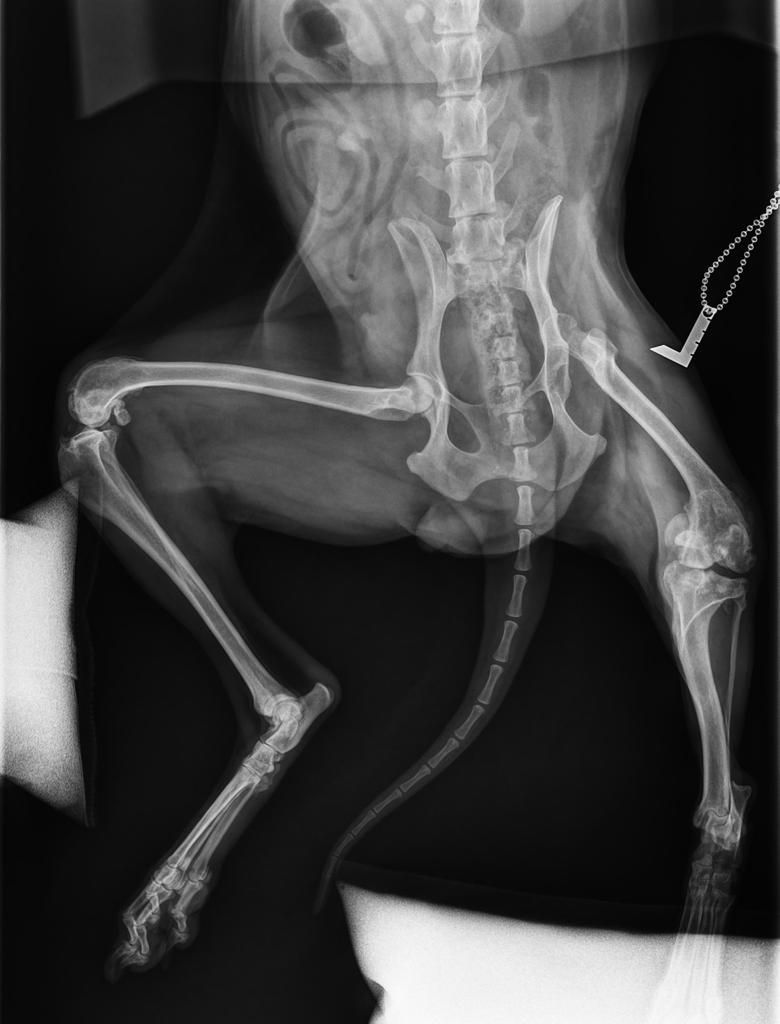

Erste Operation gelungen!

Am 16.11. ist Cosima Senta operiert worden, zuerst ist der linke Kopf des Hüftgelenksknochens entfernt bzw. Der Knochen gerichtet worden und so die Fehlstellung der Beine korrigiert worden. Beide Seiten sind leider betroffen, aber links musste zuerst behandelt werden. Zugleich wurden die Schwanzwirbel so gerichtet, dass der Knochenbau gerichtet ist, damit die Hündin einmal wieder korrekt und schmerzfrei laufen kann. Zugleich mussten die Milchdrüsen im betroffenen Bereich entfernt werden.

Diese erste Operation hat 600 € gekostet und wir danken von Herzen Lissy Schleich, die das Geld für Cosima Senta gespendet hat.

Der Tierarzt empfiehlt jetzt ein CT, um nach diesem ersten Schritt weiter planen zu können, welche Knochenschnitte und Stabilisierungen nötig sind, wie ein Neuaufbau im Beckenbereich durch Treiber gestützt sinnvoll ist. Allein für das CT müssen wir weitere 300 € stemmen, hinzukommen pro Seite 300 € für die Drei-D-Stabilisatoren/ die Treiber bzw 550 € für beide zusammen, wenn sie zeitgleich fixiert werden sollen, worüber die CT Aufnahme aufklären wird. Für uns bedeutet dies, wir sammeln weiter, damit Cosima Senta bald unbeschwert laufen und springen kann. Sie hat es wirklich verdient. Hilfe ist hier gefordert, diese knapp 900 € müssen wir erst einmal zusammenbringen. Jede Spende für die arme Maus hilft, sie hat doch noch ein ganzes Leben vor sich.